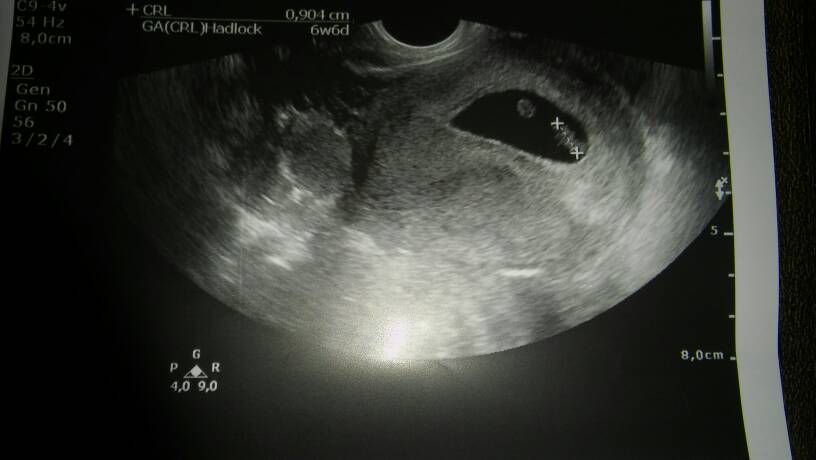

Zobacz załącznik 795776Zobacz załącznik 795777Zobacz załącznik 795778

Jest taka teoria amerykanskich naukowcow podobno w 98% skuteczna pozwalajaca okreslic plec dziecka na podstawie usg miedzy 6-8tc. Chodzi o umiejscowienie sie zarodka. U Ciebie jest z lewej strony wiec prawdopodobnie bedzie corka..... U mnie 2krotnie sie sprawdzilo. U znajomych tez. Ciekawe jak u Ciebie... Wybacz, ze pozwolilam sobie poogladac Twoje zdj usg.